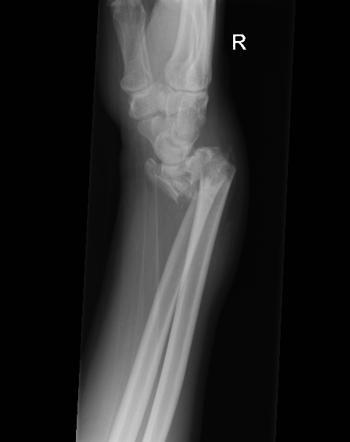

What is a Colles’ fracture?

An extra articular fracture of the distal radius within an inch of the articular surface and with dorsal displacement or angulation

What is a Smith’s fracture?

A volarly displaced or angulated extra-articular fracture of the distal radius

How is a Smith’s fracture commonly sustained?

Falling onto the back of a flexed wrist

A _________ fracture involves a volarly displaced distal radius, whereas a _________ involves a dorsally displaced distal radius

A Smith’s fracture involves a volarly displaced distal radius, whereas a Colles’ involves a dorsally displaced distal radius